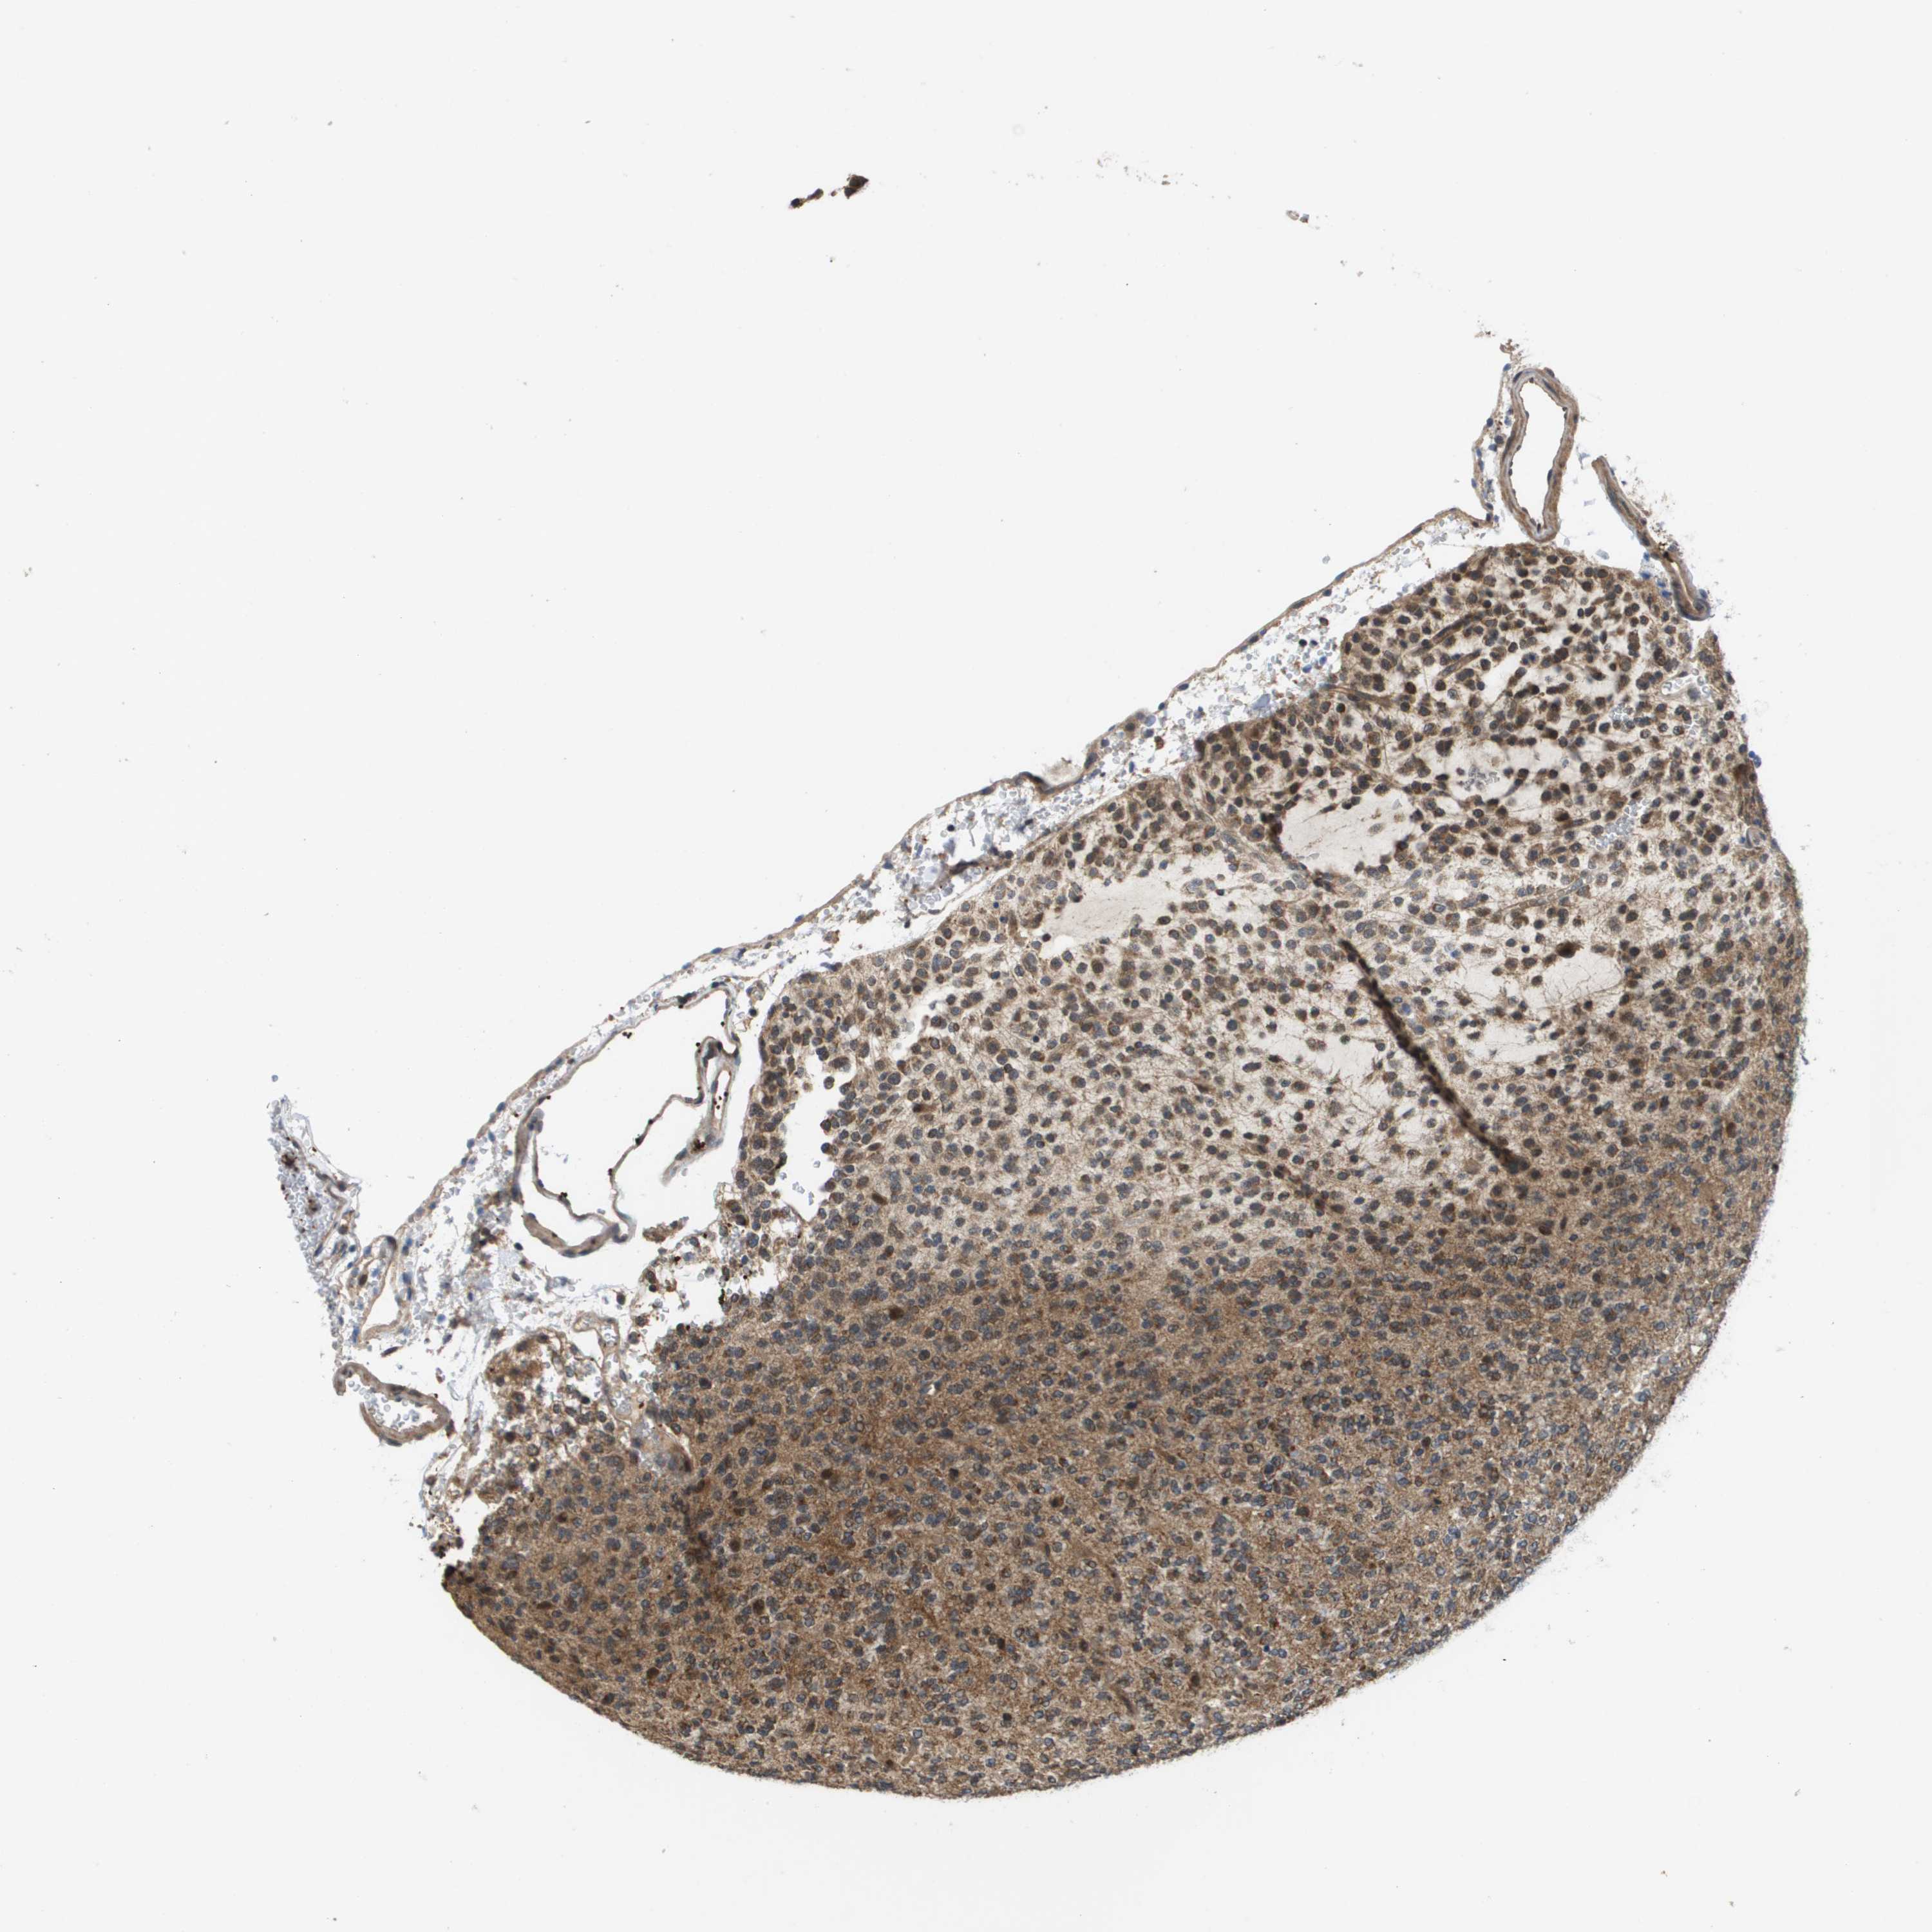

GLIOMA - Protein expressioni

A mouse-over function shows sample information and annotation data. Click on an image to view it in a full screen mode. Samples can be filtered based on level of antibody staining by selecting one or several of the following categories: high, medium, low and not detected. The assay and annotation is described here.

Note that samples used for immunohistochemistry by the Human Protein Atlas do not correspond to samples in the TCGA dataset.

Antibody stainingi

Antibody staining in the annotated cell types in the current human tissue is reported as not detected, low, medium, or high, based on conventional immunohistochemistry profiling in selected tissues. This score is based on the combination of the staining intensity and fraction of stained cells.

Each image is clickable and will lead to virtual microscopy that enables deeper exploration of all samples and also displays staining intensity scores, fraction scores and subcellular localization as well as patient and tissue information for each sample.

Antibody CAB017036

Staining

High

Medium

Low

Not detected

Intensity

Strong

Moderate

Weak

Negative

Quantity

>75%

75%-25%

<25%

None

Location

Nuclear

Cytoplasmic/membranous

Cytoplasmic/membranous,nuclear

Glioma, malignant, High grade

Glioma, malignant, Low grade